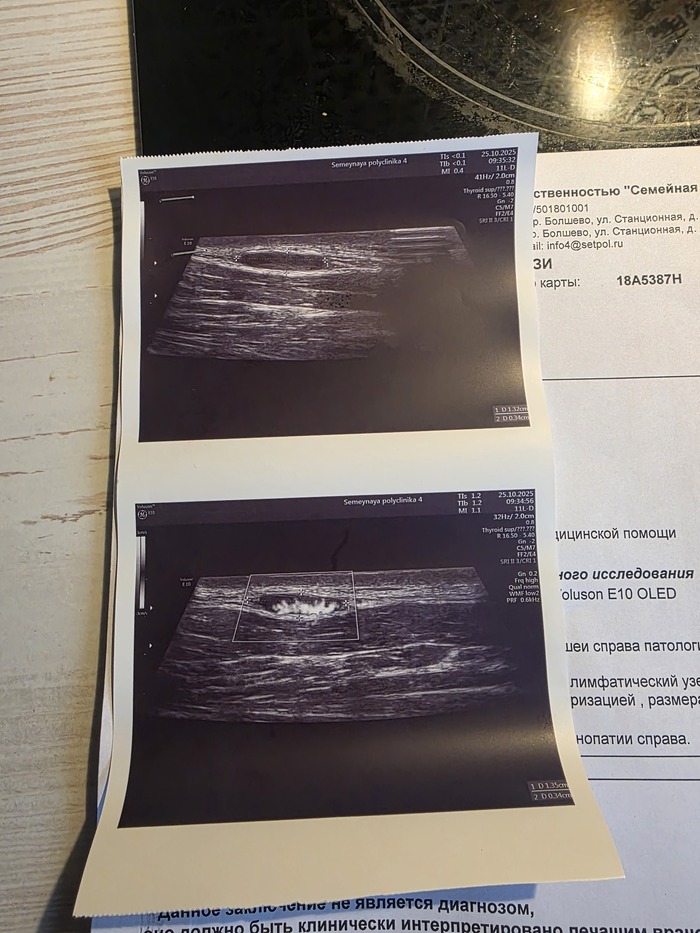

Сходил на прием к хирургу, направили на узи. По результатам УЗИ реактивная шейная лимфоденопатия. Врач УЗИ сказала что это незлокачественно.